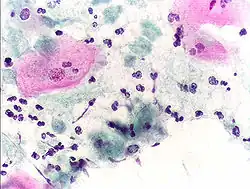

Micrograph of a Pap test showing a low-grade intraepithelial lesion (LSIL) and benign endocervical mucosa. Pap stain. -

Pap tests commonly examine epithelial abnormalities, such as metaplasia, dysplasia, or borderline changes, all of which may be indicative of CIN. Nuclei will stain dark blue, squamous cells will stain green and keratinised cells will stain pink/ orange. Koilocytes may be observed where there is some dyskaryosis (of epithelium). The nucleus in koilocytes is typically irregular, indicating possible cause for concern; requiring further confirmatory screens and tests.